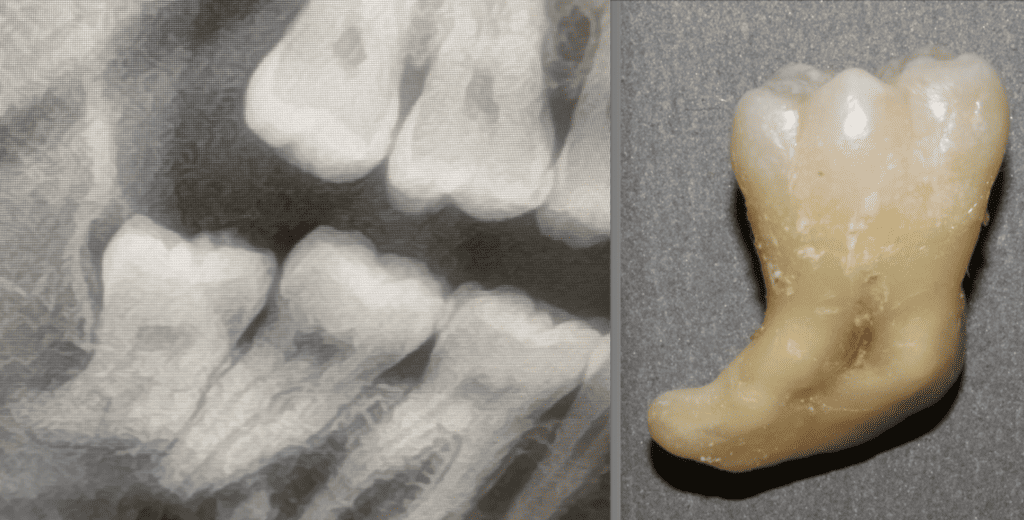

Abs was in for a day full of complex extractions today.... He is known for being so skilled and kind... we love a good Oral Surgery day. We accept referrals from 54 local practices - if you want treatment by a calm clinician - he is your GO TO!